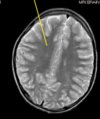

identify

multiple sclerosis

plaque (lesion) perpendicular from lateral ventricle